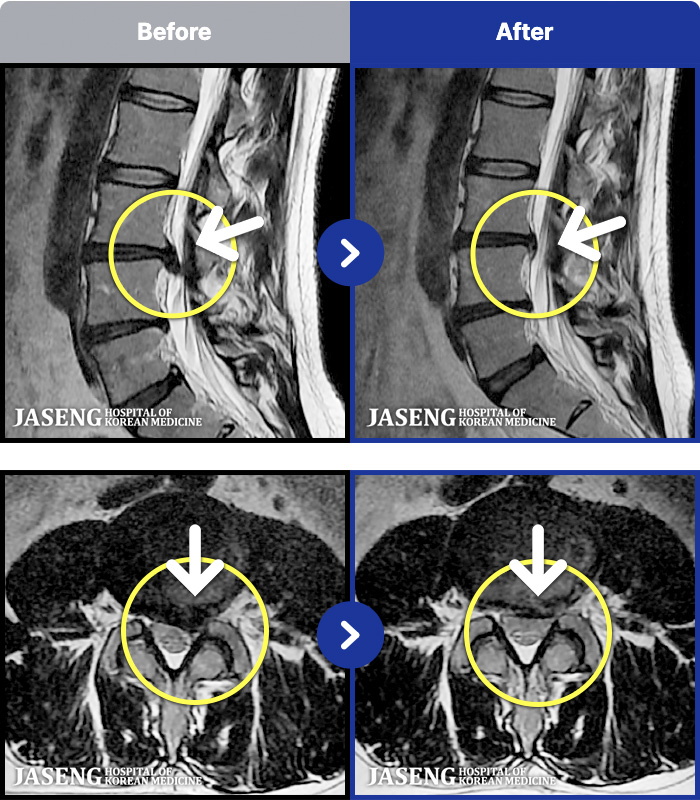

54 MRI ũ ʸ Ȯϼ.

[ϻ] 24.07.25~25.08.01